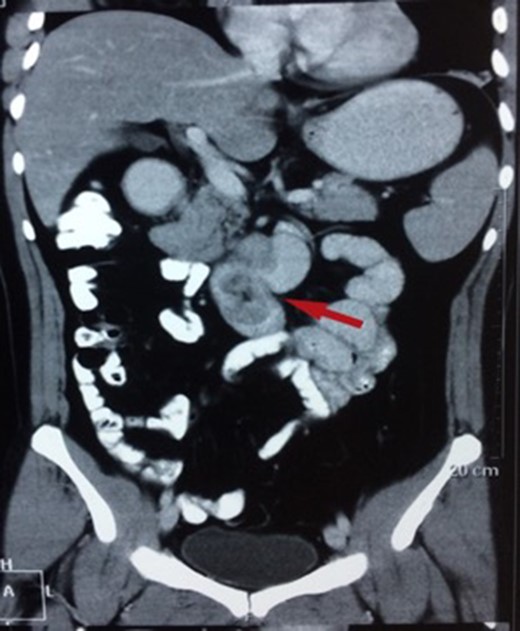

CT showing a polypoid lesion extending from the first part of the duodenum and projecting into the lumen of the second and third part.

| Case 2 | 44/M | 4 days | Malena, fatigue requiring blood transfusions | 60 × 45 mm2 mildly enhancing solid mass involving second and third part of duodenum with exophytic contour bulge likely polypoid lesion (Fig. 4) | A Large friable polypoidal lesion at junction of second and third part of duodenum | Non-specific chronic duodenitis with focal mild dysplasia | Transduodenal polyp excision (Fig. 5) | 2 | 1 | 5 |